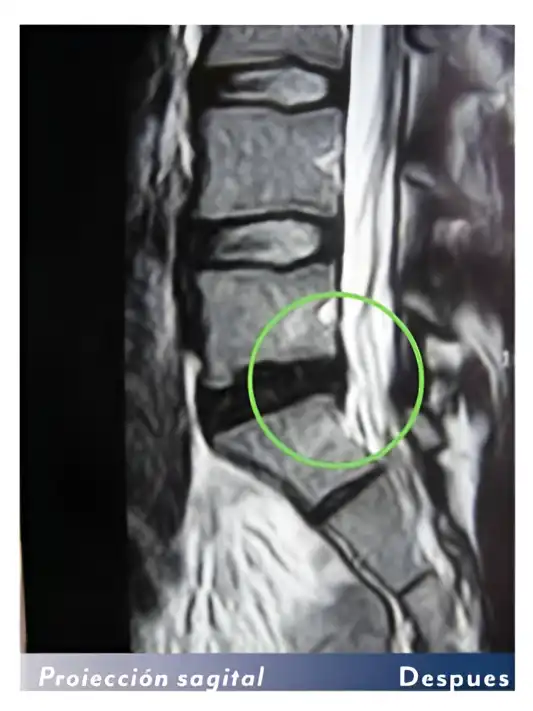

Las resonancias de un paciente antes y después de las sesiones con la bomba diamagnética. El paciente ha realizado 15 sesiones de bomba diamágnetica. Después la hernia discal ha desaparecido.

Otro ejemplo: Antes y después de 15 sesiones con la bomba diamagnética.

La hernia grande (extruida) ha desaparecido del todo (100%)